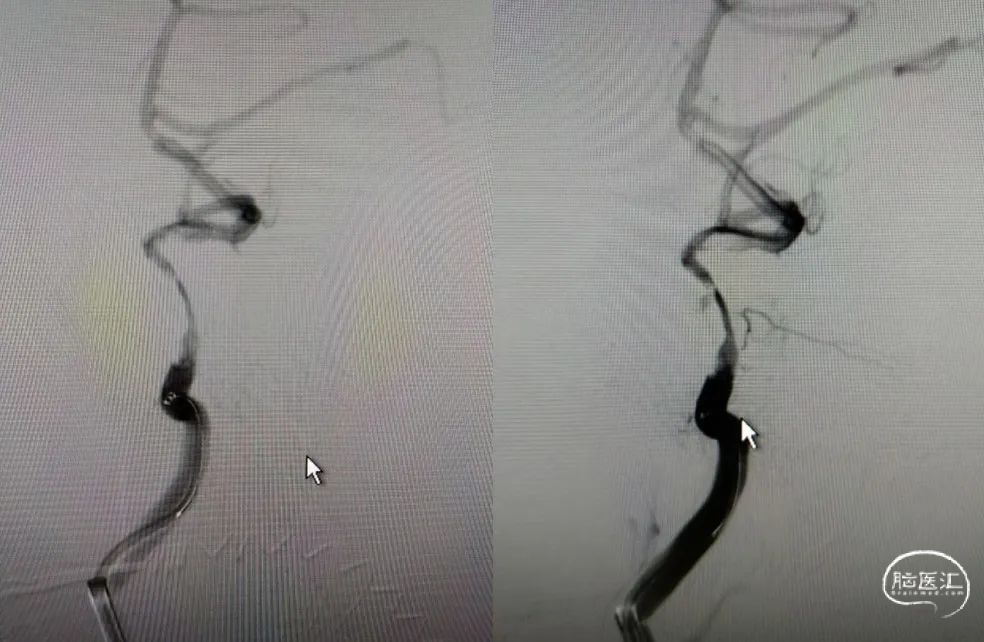

Guiding到位,导丝通过病变。

球囊通过病变。

球囊扩张过程。

扩张后造影。